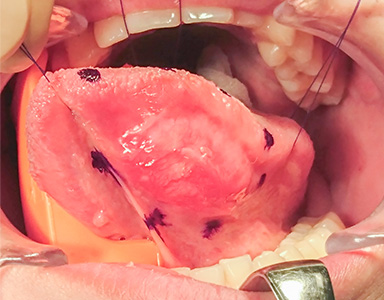

早期舌がんの治療(手術)の流れ

周囲に10mmの安全域を設定する